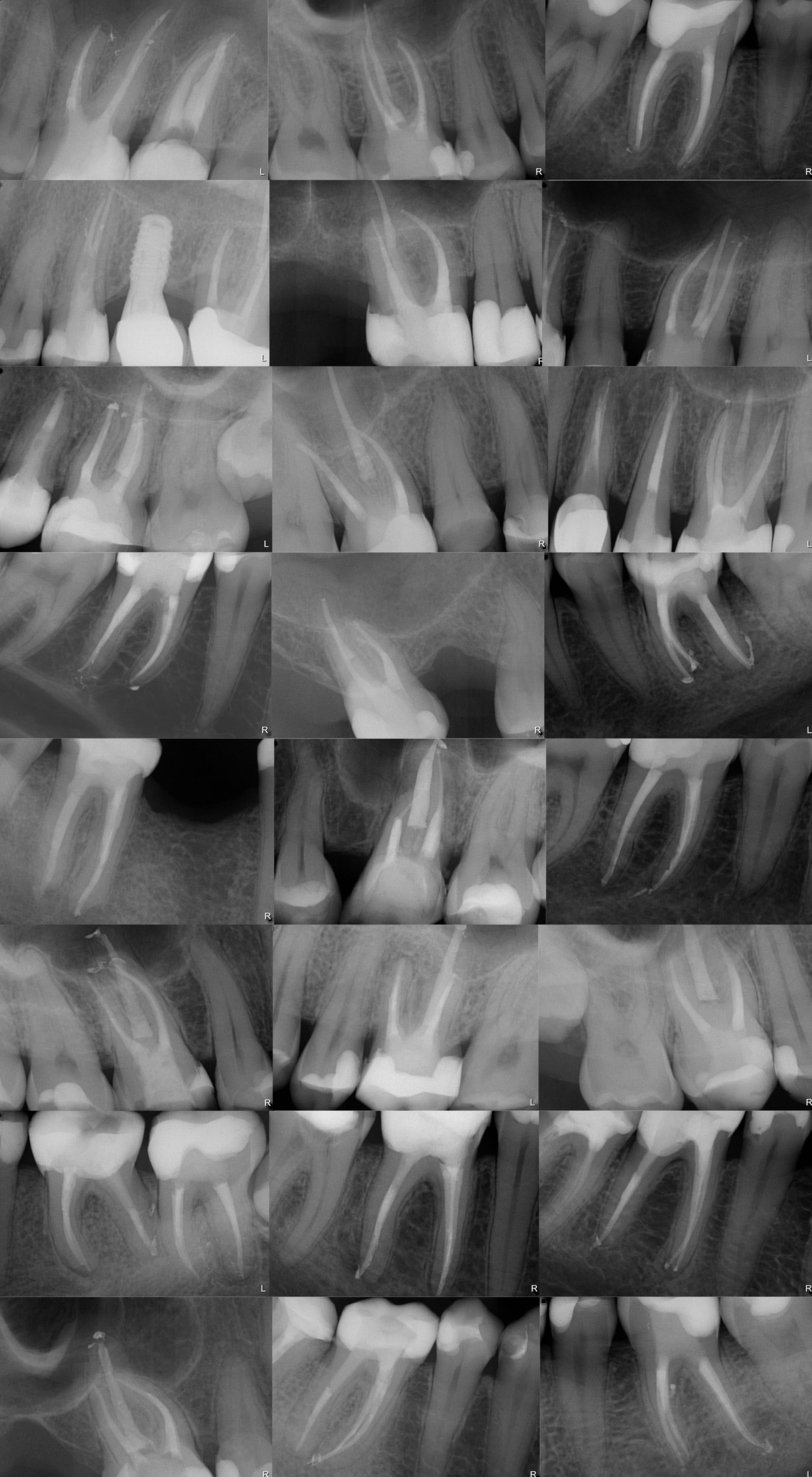

1 - diagnoza na podstawie RTG i badania klinicznego i ocena czy ząb jest potrzebny. Czy da się go skutecznie i trwale odbudować i jakimi metodami? Czy niezbędna będzie korona? Ile ma kanałów? Ile korzeni? Jak trudne to będzie leczenie i ile to potrwa? Jakie są koszty? Jakie są alternatywy… dużo pytań, ale decydując się na leczenie należy wspólnie z lekarzem omówić te kwestie.

4 - rtg potwierdzające jakość leczenia.

Każdy leczony kanałowo ząb powinien mieć odpowiednio poszerzone, zdezynfekowane, i wypełnione do samego wierzchołka wszystkie kanały. Poza tym tkanki na około zębów powinny być zdrowe, a odbudowa powinna chronić przed zainfekowaniem. Niestety wiele zębów leczonych kanałowo nie spełnia tych norm. Podstawowym badaniem potwierdzającym prawidłowość leczenia endodontyczncgo jest zdjęcie RVG, a w bardziej skomplikowanych przypadkach CBCT (cone beam computed tomography - tomografia komputerowa wiązki stożkowej). Na tych badaniach oceniamy jakość leczenia i jeżeli jakiś element budzi nasze wątpliwości kwalifikujemy ząb do re-endo.

Podczas re-endo często jest konieczność wykonywania dodatkowych, wymagających zabiegów takich jak udrażnianie zwapniałych kanałów, usuwanie złamanych narzędzi, wcementowywanie/rozwiercanie wkładów koronowo-korzeniowych, zamykanie perforacji, usuwanie zainfekowanych materiałów z kanałów. Czasami, aby to wszystko było możliwe trzeba usunąć najpierw koronę lub most. Wszystko to sprawia, że ponowne leczenie endodontyncze może być bardzo czasochłonne i w skomplikowanych przypadkach odbywa się na kilku wizytach. Czasami może się również okazać niemożliwe ze względu na wcześniejsze powikłania.

W takiej sytuacji opracowujemy i wypełniamy kanał najgłębiej jak to możliwe, a następnie planujemy wykonanie resekcji wierzchołka korzenia - czyli zabieg chirurgiczny w wyniku którego zostaje odcięty i usunięty zainfekowany fragment korzenia, wraz z zmienionymi chorobowo otaczającymi tkankami.